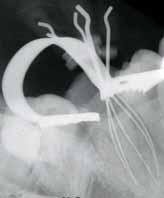

posteriorly on the left palate till the posterior vibrating line. There was no pointing of the lesion. IOPA and occlussal radiographs were taken (Fig1a & b). The IOPA revealed a huge radiolucent lesion with diffuse margins in relation to the periapical region of the upper left lateral which had a root canal filling and a separate smaller radioluscent periapically to the adjacent central incisor also. The occlussal radiograph showeda large radiolucent lesion on the palatal aspect in relation to the upper left lateral. It was decided to retreat the case and the patient was advised of the poor prognosis of the tooth.

Fig 1a: First visit (IOPA) Fig 1b: first visit (occlussal) Fig 2a: Pre obturation 14 months (IOPA) Fig 2b: Pre obturation 14 months (occlussal)

hypochlorite and hydrogen peroxide and then washed with saline. A closed dressing with calcium hydroxide was given and patient recalled after one month. Thereafter, periodic monthly appointments were given where the canal was irrigatedand closed irrigation with calcium hydroxide was given. After around 14 months after the first visit the swelling was completely absent and patient reported no pain. The periapical radioluscency was still present though localized to the periapical and reduced to around 5mm in diameter (Fig2a & b). This time the canals were obturated using lateral condensation technique (Fig 3). And the patient recalled after six months for a review. Six months after obturation it was seen that the periapical radioluscencywas almost absent with a mild crescent shaped radioluscent around the apex (Fig 4a & b). The patient had no symptoms to report. During the intervening six months the patient had crowns made to correct the discoloration. The patient was recalled after a period of six months to further review the healing.

One year after obturation the patient had absolutely no signs and no symptoms. The occlussal radiograph and periapical radiograph showed a very thin crescent shaped radioluscency at the apex (Fig 5).